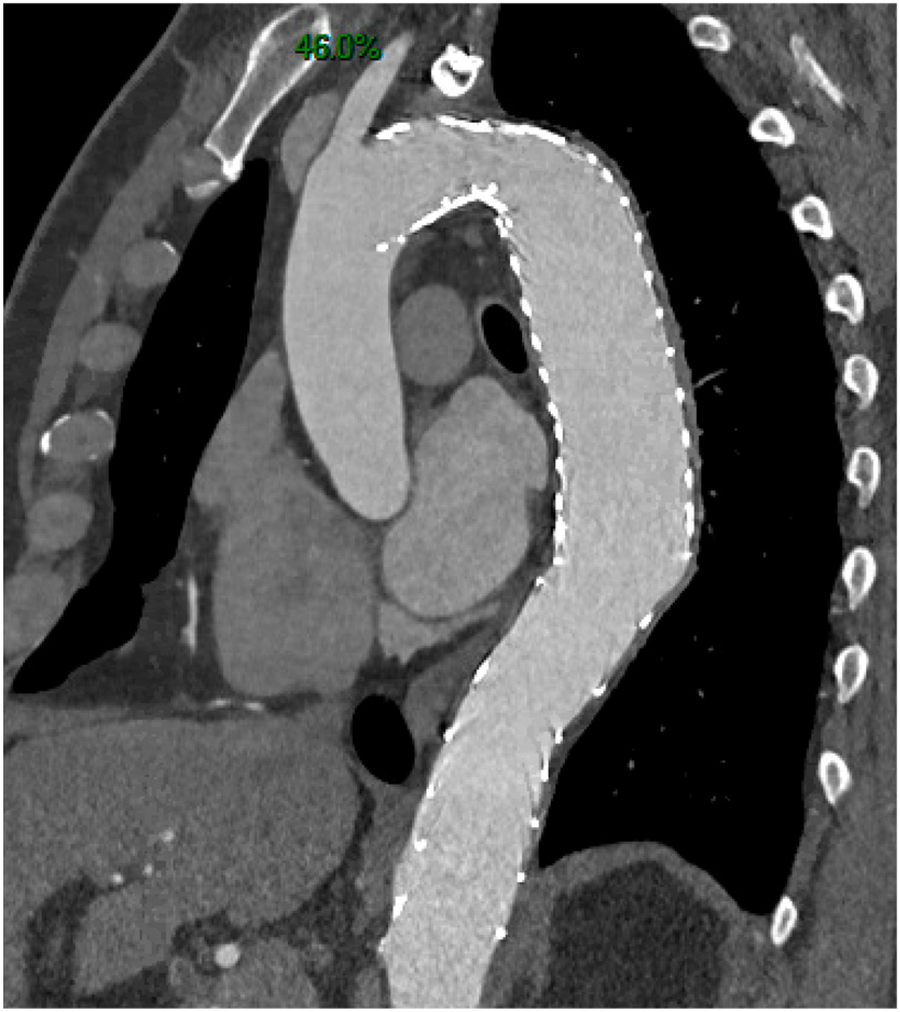

Radiologic aortic analysis consisting of aneurysmal progression of aortic diameters (defined as a 5 mm increase in the aortic diameter within 6 months or an aortic diameter reaching 50 mm during follow-up) and aortic remodeling [FL thrombosis and reapposition of the intimal flap (Figure 1)].

Figure 1

Complete aortic remodeling with false lumen shrinkage.